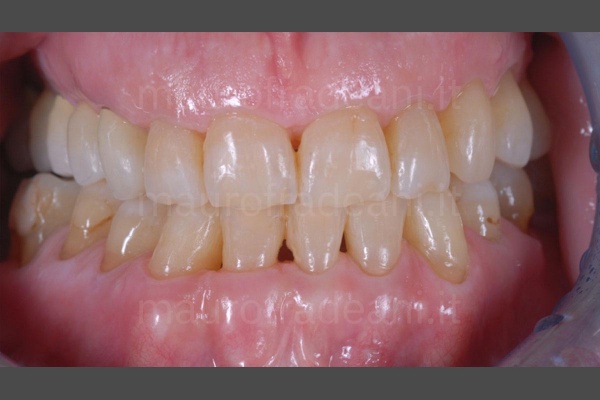

1/4: The patient presents generalized lack of aesthetics in terms of color and alignment, as well as marked dental wear.

2/4: The intraoral view shows inadequate tooth shapes and sizes.

3/4: The aim of this esthetic-functional rehabilitation, involving both arches, was the restoration of suitable tooth shapes and dimensions, while achieving a correct occlusion.

4/4: The final result of the treatment, perfectly integrated in the patient's mouth, fully satisfies all expectations.